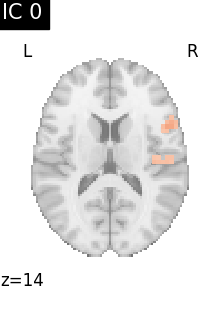

Finally, we plot the map for each ICA component separately

for i, cur_img in enumerate(iter_img(canica_components_img)):

plot_stat_map(

cur_img,

display_mode="z",

title=f"IC {int(i)}",

cut_coords=1,

vmax=0.05,

vmin=-0.05,

colorbar=False,

)

show()